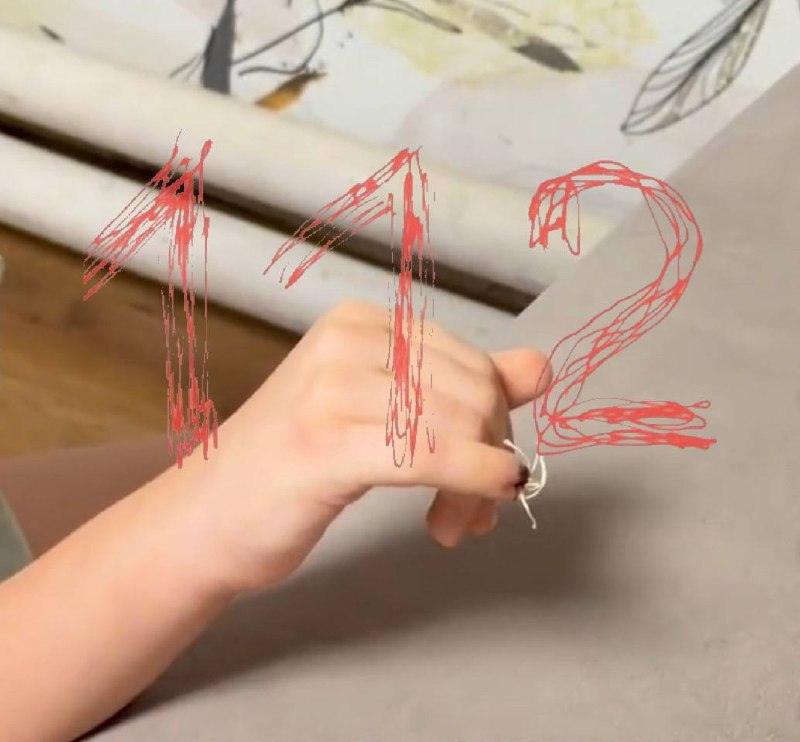

В детском саду №83 города Бийска произошел инцидент, в результате которого 7-летняя девочка получила тяжелую травму пальца. По словам матери ребенка, Анастасии, инцидент произошел во время занятий физкультурой. Девочка прижалась к стене и положила руку на открытую дверь, которую затем закрыл другой ребенок, прищемив палец.

Сотрудники детского сада, по утверждению матери, не вызвали скорую помощь, ограничившись сменой повязки. Родителям сообщили, что без их присутствия вызвать медиков нельзя. Девочку доставили в больницу, где ей наложили швы, однако травма оказалась серьезнее, чем предполагалось. Сейчас ребенку грозит ампутация пальца из-за повреждения кости.